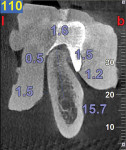

A CBCT study shows hard tissues and the shadow of soft tissues as long as they are surrounded by hard tissue. The pulpal tissue of the teeth is not visible, but the outline of the pulp chamber is visible. The mandibular nerve is not visible, but the cortical bone surrounding it does appear on the CBCT, making it possible to deduce where the mandibular nerve is expected to be. The proposed visualization technique allows very strong contrast to create a negative, much like the just-discussed image of the mandibular nerve. The concept is rather simple; VPS impression material can be radiopaque, but not all materials are radiopaque to the same extent, and some are not radiopaque at all (Figure 2). The patient wears a VPS impression during the CBCT exposure (Figure 3 and Figure 4). This can be the actual impression, or a dedicated impression made from a diagnostic cast (Figure 5). This simple technique shows a very distinct space, which is visible between the VPS material and the bone (Figure 6 and Figure 7). For the purpose of the 3D Click Guide fabrication, this space would otherwise be measured with the bone-sounding technique, as discussed in Part 1 of this series. Because the surface of the VPS impression visible in the CBCT image is exactly similar to the surface of the cast, the two can be exactly superimposed. Within the CBCT software, simple measurements can be made. Those measurements are made at the same locations as those used when bone sounding. Those measurements are then transferred to the cast. Additional information—eg, location of the mandibular canal—can be extrapolated and drawn as needed (Figure 8 and Figure 9).

An 80-year-old woman, who presented with a missing lower molar, requested an implant-supported replacement. Advanced periodontal bone loss at site No. 19 resulted in considerable resorption of the alveolar ridge after healing. Although simple bone sounding is the preferred data-gathering technique for the author, in this case, there was insufficient information available to safely perform an osteotomy. The decision was made to gather additional information with a CBCT study.

The cast was sectioned 4 mm distal of tooth No. 20. The data from the corresponding cross-sectional cut were transferred to the cast. The ideal buccolingual axis was drawn onto the cast, based on a screw access hole in the central fossa of the future crown. A small hole was drilled at the desired location of the shoulder of the implant. The pin of the Bucco Lingual Positioner (BLP) was placed in the hole, and the central groove of the BLP was lined up with the drawn implant axis. A drop of fast-setting cyano-acrylate glue was applied to lock the BLP in place (Figure 11). The opposing part of the cast was adjusted and the cast was reassembled into the Accu-trac tray. At this point, the buccolingual axis and the top of the implant were irreversibly set, and the mesiodistal could be determined without the risk of making inadvertent changes in the buccolingual plane. The correction slot in the crossbar of the wing assembly fits snugly over the top of the BLP, allowing mesiodistal rotation and mesiodistal translation (Figure 12). Once the correct mesiodistal position was selected, the wings were irreversibly connected to the vacuformed carrier by means of ortho-acrylic (Orthoresin, DENTSPLY International, www.dentsply.com); then the cross-sectional bar was removed, allowing placement of a rotation block. The surgical guide was placed in the mouth and a periapical radiograph was exposed (Figure 13). Note that if the buccal and lingual wings overlap and appear to be one, the radiograph has been taken exactly perpendicular to the ridge, allowing a decision to be made because the image is of acceptable diagnostic quality. In this case, the trajectory was as desired, and the 0º rotation block was selected, as there was no need for rotation adjustments by means of the 3º or 7º rotation blocks (Figure 14). The surgical guide was sterilized in a cold sterilizing solution and the surgery was performed per the manufacturer’s drilling protocol. A 8.5-mm x 4.3-mm implant (NobelActive™ 4.3 x 10 mm, Nobel Biocare, www.nobelbiocare.com) was placed as planned (Figure 15).